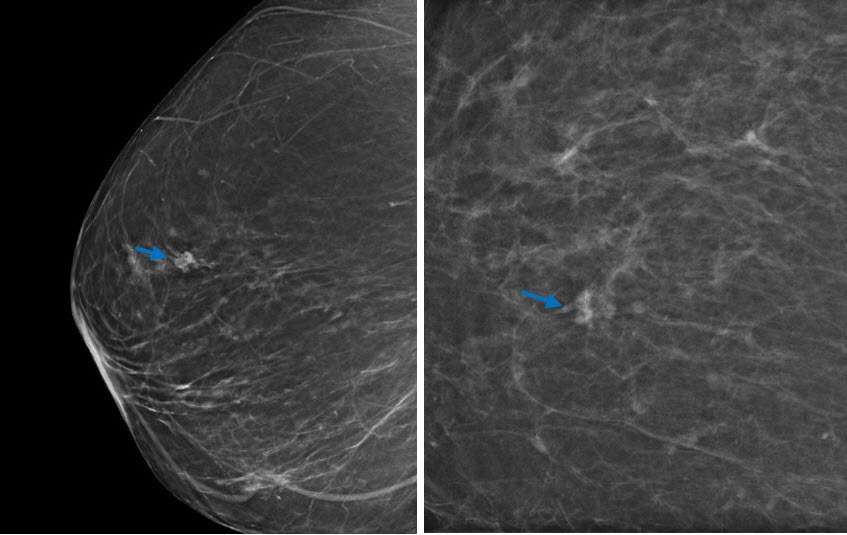

Mammography:

Radial sclerosing lesions are often identified incidentally on screening mammograms. There is robust evidence that digital breast tomosynthesis improves the detection and characterization of RSLs compared to digital mammography (4). The radiographic appearance of RSLs may be indistinguishable from that of invasive carcinoma, thus needle biopsy is essential in excluding malignancy.

Radial sclerosing lesions may be multiple and/or bilateral. The most typical appearance is an architectural distortion or the “black star” configuration, which is defined as spiculations radiating from a central point without a central mass (Fig 1a). However, the presence of a radiolucent center is not reliable in differentiating a RSL from malignancy (1). Less frequently, RSLs may appear as a stellate opacity or the “white star,” which is described as a mass with spiked linear extensions (3).

It is most rare for RSLs to present as grouped microcalcifications. The calcifications in these lesions demonstrate nonspecific morphology and are usually associated with coexisting proliferative changes and sclerosing adenosis within and surrounding the lesion(3).